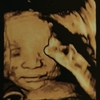

宝妈也在问类似的问题